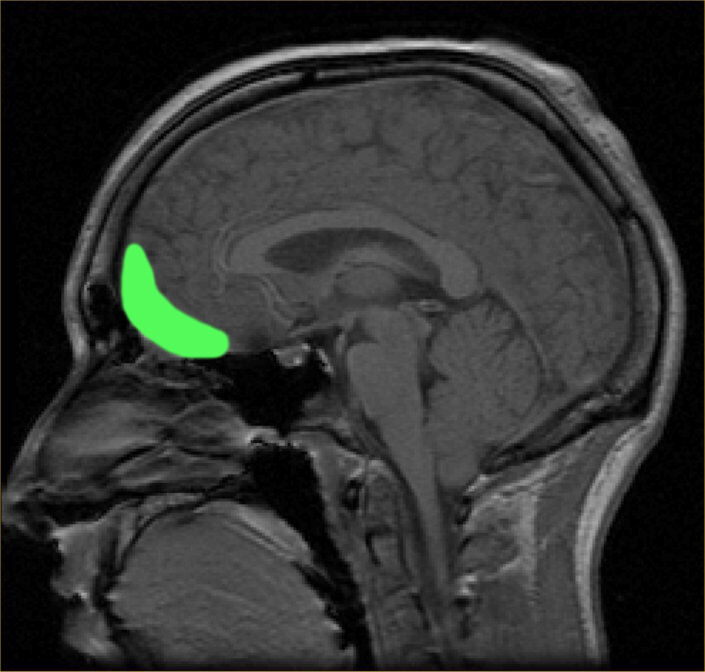

Испоставило се да је код оних који су годишње 1000 или више пута урадили главом лопту постоје промене у кортикалном интерфејсу сиве и беле масе у орбитофронталној регији мозга, која се налази тик иза очију.

"Код здравих људи прелаз између ткива сиве и беле мождане масе је јасан и веома лако уочљив на снимцима магнетне резонанце", појаснила је научница Џоан Сонг, која је учествовала у анализи снимака магнетне резонанце.